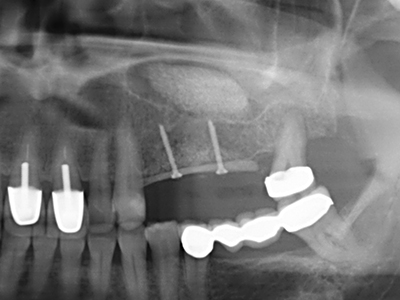

Piezosurgery has additional advantages when harvesting bone blocks. In addition to the high precision with osteotomy described above, the use of the thin saw tips specifically minimizes loss of material. Greater loss of material during harvesting can be expected with the thicker instrument tips, particularly when using Lindemann drills (Lakshmiganthan, Gokulanathan et al. 2012). The basal separation, which is necessary particularly for retromolar block transplants, is simplified by specially designed rectangular saws, with the result that piezosurgery is viewed as a precise, simple and safe procedure for harvesting retromolar bone blocks (Happe 2007) (Fig. 1-12).